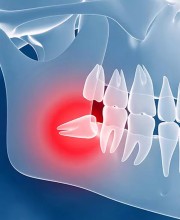

آیا شما هم از مشکلات دندانهای از دست رفته رنج میبرید؟ آیا دندانهای شما از نظر زیبایی یا عملکرد دچار مشکل شدهاند؟ اگر جواب شما بله است، وقت آن رسیده که راهحل بلندمدت و مؤثری را پیدا کنید.

ایمپلنت دندان، نهتنها ظاهری طبیعی و جذاب به شما میدهد بلکه به طور چشمگیری کیفیت زندگی شما را بهبود میبخشد. این روش پیشرفته میتواند جایگزینی دائمی برای دندانهای از دست رفته باشد، که به شما اجازه میدهد دوباره با اعتماد به نفس بخندید، بخورید و حرف بزنید.

با ایمپلنت دندان، نه تنها ظاهر خود را بهبود میبخشید بلکه سلامت دهان و دندان شما هم به شکل قابل توجهی بهتر میشود. ایمپلنتها از تحلیل استخوان جلوگیری میکنند و باعث حفظ ساختار طبیعی فک و دهان میشوند.

آیا ایمپلنت دندان برای شما مناسب است؟

این سوال ممکن است در ذهن شما به وجود آمده باشد. خبر خوب این است که ایمپلنت دندان تقریباً برای تمامی افرادی که دندان از دست دادهاند، مناسب است. پزشکان ما با معاینه دقیق، مناسبترین گزینهها را برای شما پیشنهاد خواهند داد.